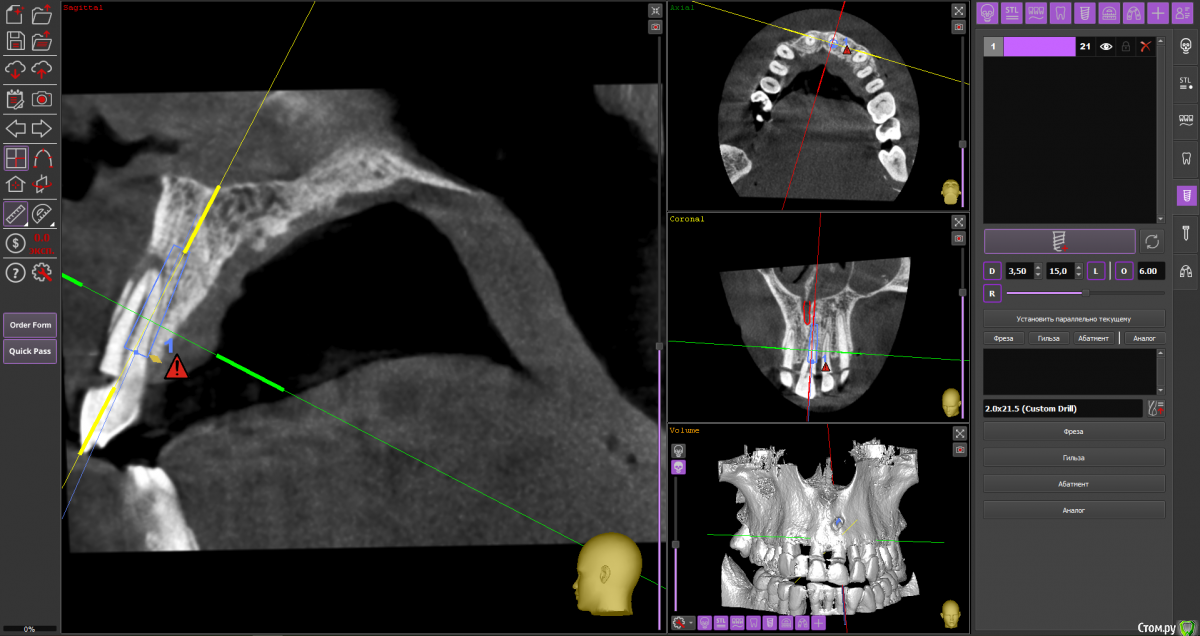

almaz7888 Опубликовано 28 января, 2021 Поделиться Опубликовано 28 января, 2021 Доброе утро коллеги! Планирую одномоментную имплантацию в область 2.1 зуба ( AnyRidge 3.5*11.5). В области апекса костный дефект. Думаю заполнить ксенографтом и перекрыть резорбируемой мембраной 1.5*2.0. Думал насчет спейсера Стоит ли такой имплант сразу нагрузить? или же лучше сделать адгезивный мост. Ссылка на комментарий

alboard Опубликовано 28 января, 2021 Поделиться Опубликовано 28 января, 2021 В том положении, которое на кт, сомневаюсь, что получите торк и сможете нагрузить... Взять подлиннее, поставить небнее и заглубить еще 4 Ссылка на комментарий

Irouil Опубликовано 28 января, 2021 Поделиться Опубликовано 28 января, 2021 Винт длиннее, выход в резцовый, стт, временная коронка 1 Ссылка на комментарий

almaz7888 Опубликовано 28 января, 2021 Автор Поделиться Опубликовано 28 января, 2021 Спасибо, тогда возьму 3.5*15. А резцовый нерв коагулирую и заполняю канал графтом или же можно без прижигания обойтись? Ссылка на комментарий